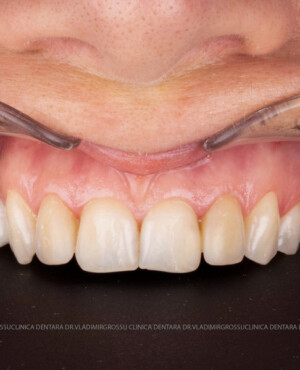

Cazuri clinice

Caz 1